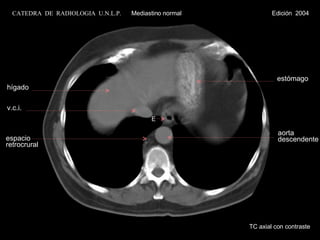

TC axial con contraste E hígado v.c.i. estómago espacio retrocrural aorta descendente CATEDRA  DE  RADIOLOGIA  U.N.L.P.   Mediastino normal  Edición  2004

TC axial concontraste E hígado v.c.i. estómago espacio retrocrural aorta descendente CATEDRA DE RADIOLOGIA U.N.L.P. Mediastino normal Edición 2004